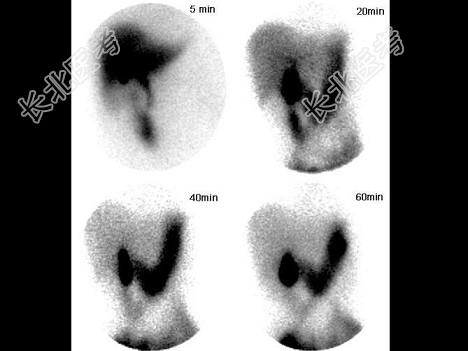

- 单项选择题某患者嗳气、反酸、上腹部不适3年,行99Tcm-EHIDA显像, 5分钟时饮牛奶300ml,诊断是 ( )

D、十二指肠胃反流